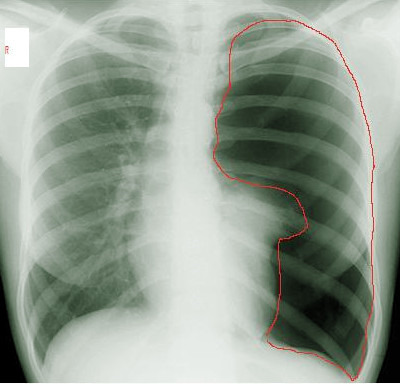

그림